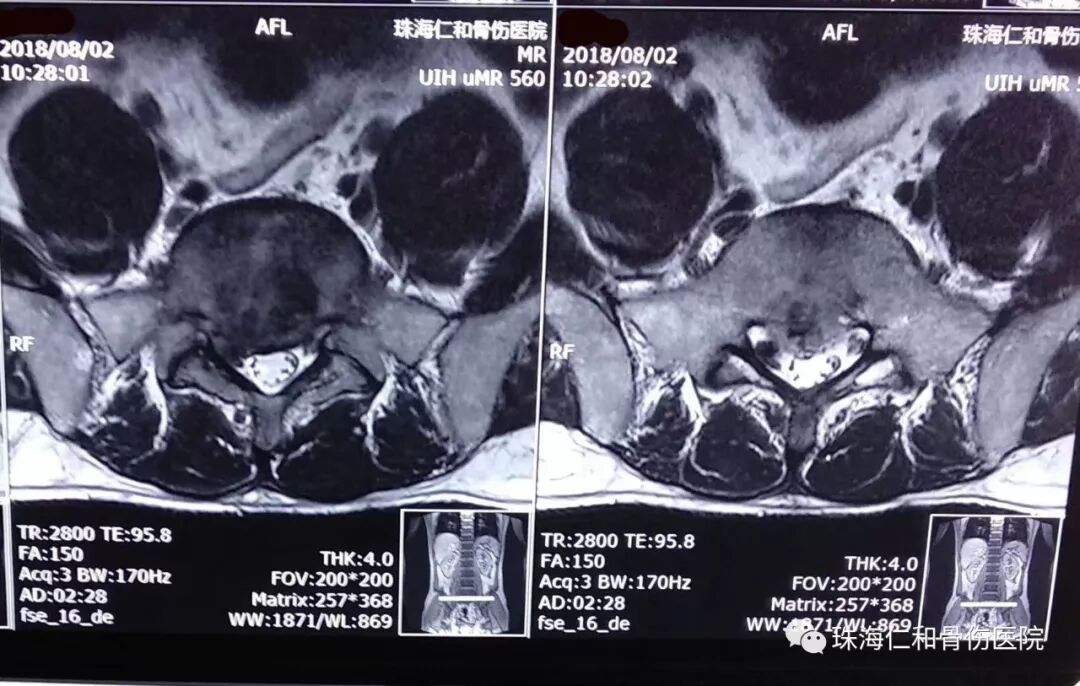

腰腿痛,工作和生活常见多发病。仁和骨伤医院脊柱专科开展特色手法、针灸,中药烫包和中药泥灸等中西医结合系列保守治疗。使得众多腰腿痛(腰椎间盘突出症)病患者好转满意而归。然而总有一些顽固腰腿痛,需要通过特殊治疗手段解决。就像我们这位阮老师,出现腰痛和右下肢麻痛反反复复已经十多年,诊断是腰椎盘突出症,也曾到省内和市内各大医院求医问诊过,但都无法使得腰腿痛得以解除,教书育人工作、日常生活都受到影响。来到仁和骨伤医院,住院伊始就抗拒手术治疗,于是仁和的脊柱专家倾情为他多措并举的保守施治,可是因为椎间盘突出严重,效果欠佳,阮老师经过对微创手术充分了解,同意仁和医院为他设计的微创手术治疗方案,脊柱孔镜椎板间入路髓核摘除、神经根管扩大、纤维环成型术。手术相当顺利,术后阮老师就觉得腰痛和腿痛症状消失了,术后第二天就可以带腰围保护下床开始活动,阮老师往日久违的笑容又回来了。相信不久的日子,在仁和专业的康复指导下,阮老师很快会回到工作岗位、开始崭新的生活。